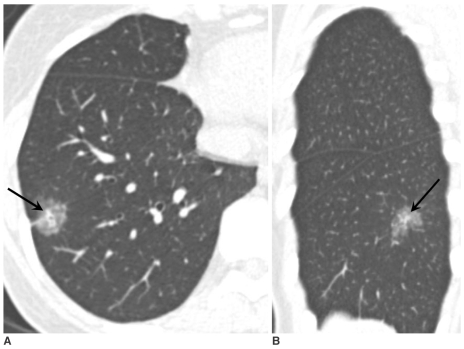

圖示為CT圖像顯示右上葉 21 mm 混合結(jié)節(jié)性磨玻璃影